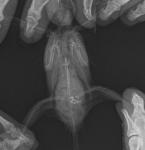

Здравствуйте! Сделали мы снимок , жду описания и реультатов от вас

post-64778-1454950882_thumb.jpg

post-64778-1454950890_thumb.jpg

1.Липома отдельно

2.Две опухоли (одна из них на почках ,вторая-может да.может нет).

Вопрос такой-хоть на чем нибудь птице становилось легче?

Я бы назначала сейчас спазмолитики(дроттаверин),нестероидные противовспалительные(ибупрофен,потом пироксикам), гепатопротекторы помощнее (урсосан). Преднгизолон ампульный.

Липойку и гепатовет- убрала бы, потому что... можно жить с липомой долго. А с опухолью- сами понимаете.